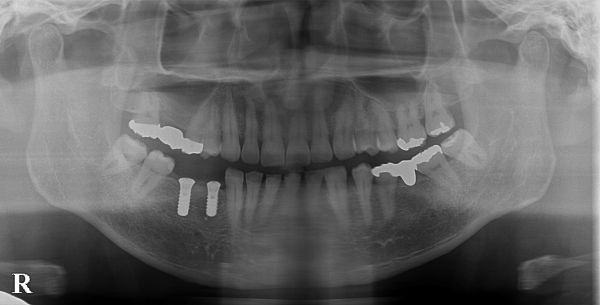

処置時間は40分程度で問題なく終了しました。処置後のレントゲン写真がこちらになります。

被せ物(ジルコニア)が出来上がってきましたので、微調整を行い、お口の中にセットしました。セット後のお口の中の写真とレントゲン写真がこちらになります。